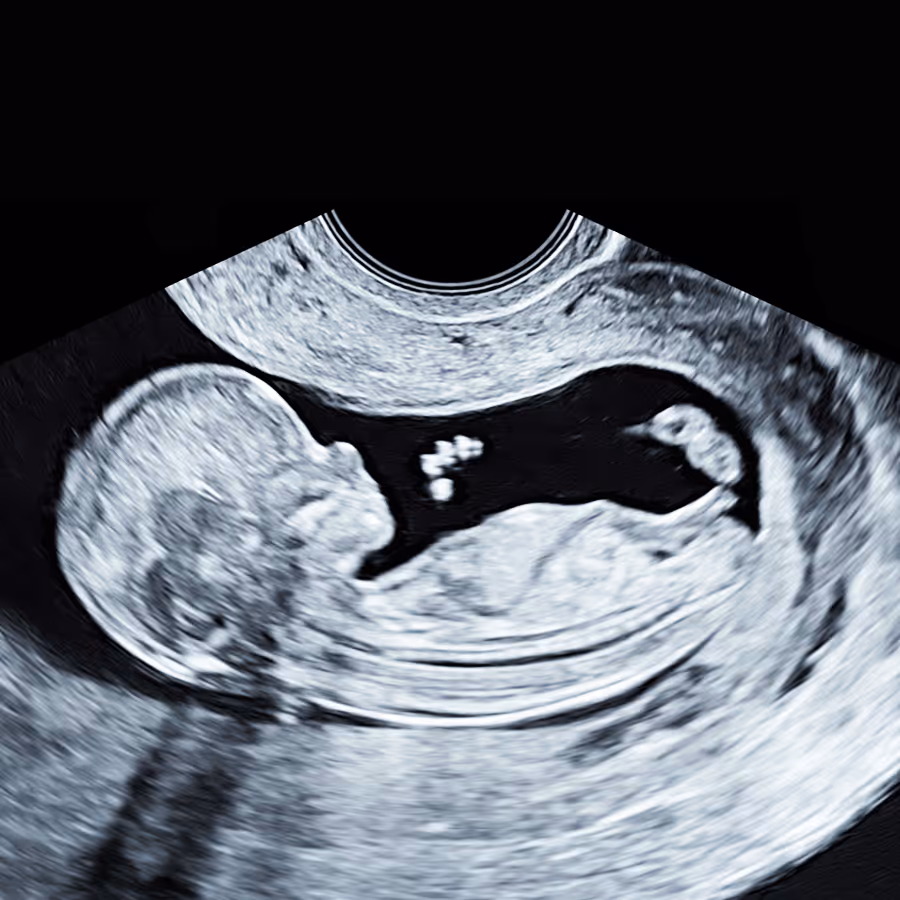

A second visit is usually arranged once the NIPT results are back, typically around 12–13 weeks. At this stage, a more detailed early anomaly scan is performed, with particular attention to the baby’s heart and other organs, and the findings from both the scan and the NIPT are reviewed together. If the NIPT result is high chance, and/or the fetus has persistent increased NT or structural anomalies, the options for invasive diagnostic testing (CVS or amniocentesis) are then discussed.